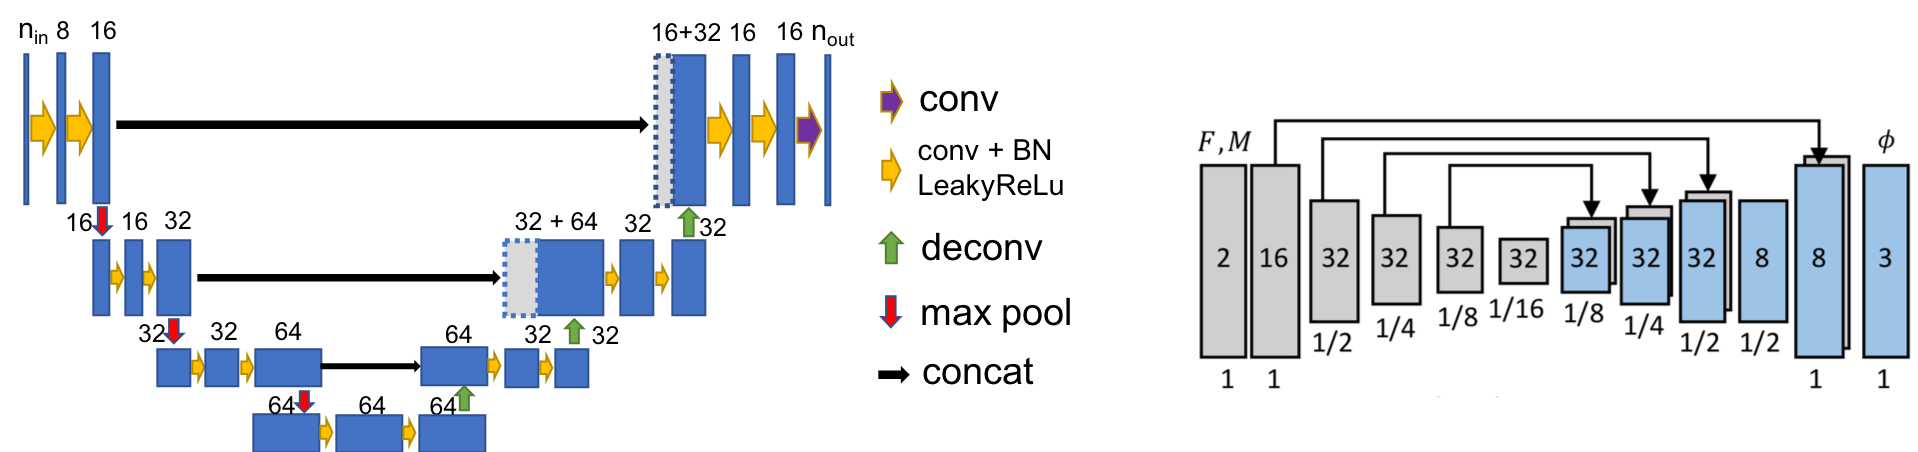

2 Method

Our goal is to improve registration and segmentation accuracy when few manual segmentations are available for a large set of images by jointly learning a segmentation and a registration network. Fig. 1 illustrates our approach consisting of two parts: weakly-supervised registration learning (solid blue lines) and semi-supervised segmentation learning (dashed yellow lines). Our loss is the weighted sum of the registration regularization loss (), the image similarity loss (), the anatomy loss () penalizing segmentation dissimilarity, and the supervised segmentation loss (). The losses {, , } drive the weakly supervised learning of registration (Sec. 2.1) and the losses {, } drive the semi-supervised learning of segmentation (Sec. 2.2). Sec. 2.3 details the implementation.

2.3 Implementation Details

Losses: Various choices are possible for the intensity/anatomy similarity, the segmentation, and the regularization losses. Our choices are as follows.

Networks: DeepAtlas can use any CNN architecture for registration and segmentation. We use the network design of [2] for registration; and a customized light 3D U-Net design for segmentation with LeakyReLU instead of ReLU, and smaller feature size due to GPU memory limitations.